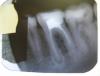

ElenDent Опубликовано 10 декабря, 2012 Поделиться Опубликовано 10 декабря, 2012 Собственно, в клинике появился данный инструмент и хотелось бы поделиться впечатлениями.Первые ощущения совершенно необычные - будто с машины пересел на вертолет: файл не вращается - дрожит, при этом постоянно ручьем льется гипохлорит. Жутко непривычно. Сам САФ очень нежный и капризный, очень не любит выметающих движений и дентинных наплывов в устьях - тут же начинает мяться и рваться. Добавим сюда минимальную анимацию файла в канале (ввели, подождали, вынули, ввели снова и так 4 минуты). И создается ощущение чего-то неправильного и шаманского. Теперь собственно слайды. Прошу прощение за гадкое качество, постараюсь исправиться.Первый пациент пришел в клинику с желанием полечить 46. Полечить не удалось, решили подготовить под протезирование 45. В каналах был одинокий гуттаперчевый штифт и паста. Распломбировал - протейпер Д3 + ручные + хлорка + УЗ. Закрыл с кальцием, стал ждать чудо-инструмент.Чудо инструмент приехал. Отработал в канале 3 минуты файлом 1,5мм.Запломбировал гуттаперча/AH+, латеральная компакция. Вторая пациентка. Плановая подготовка к протезирования, плановый ретрит 46. В каналах гуттаперча, в перемушку с чем-то резорциновым (зуб бледно розовый).Распломбировал - протейпер Д3 + ручные + хлорка + УЗ.Увидел остатки пломбировочного материала в дистальном, плюнул на рекомендации Соломонова по кривой обучения - влез SAFом. Проработал около 2 минут, файл прожевало и скрутило пополам. Из канала SAF извлекся довольно быстро и без экстрима - подцепил пульпоэкстрактором. Упаковал в устья кальций, сверху тефлон и СИЦ. Как потом выяснилось, SAF свою работу выполнить успел. Первые впечатления:1. Очень сложно переучиваться. Всё время хочется добавить выметающих движений. Ассистент тоже бесится - подобраться слюноотсосом очень сложно, а хлорка всё бежит и бежит.2. Жутко бесит процедура промывания помпы в конце смены. Хотя после Вектора возни больше.3. Сейчас очень напрягает цена этого чуда - 30 евро. Учитывая, что сдуру он ломается на раз-два - стоимость канала выходит приличная. Надеюсь, Соломонов не врет и потом файла будет хватать на подольше.4. Он реально вымывает гуттаперчу. В первом случае я её даже в бинокуляраы не видел, а САФ ошметков довольно много вымыл.5. Очень легко извлекается. Прям отлично. 4 Ссылка на комментарий